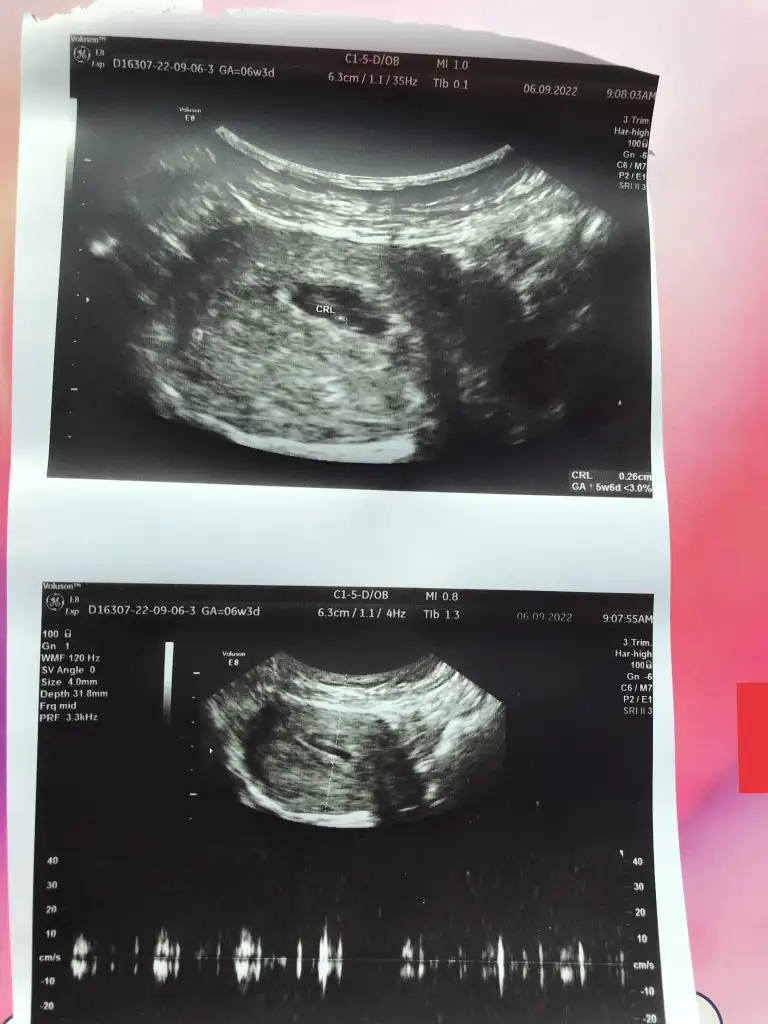

Kızlar ben kontrolden geldim karından baktılar hem bebeği hem kalp atışını gördüler ama doktor çok emin olamadı kalp atışından bide vajinal bakmak istedi vajinal bakınca daha net bir şekilde kalp atışı var dedi çok şükür cihazları zayıf olduğundan sanırım biraz görüntü kalitesi de zatıf ama paylaşayım![]()

2 hafta sonra kalbini dinlemeye gidicez inşallah, haftasıyla uyumluymuş bi sıkıntı olmadı şükür

Kalp atışları yeni oluşmaya başlamış az atıyordu ama biraz dinletti yakalayabildiği kadarını![]()